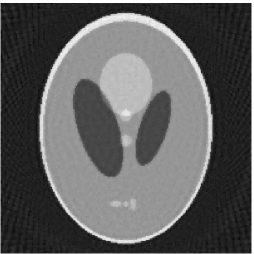

Furthermore, we used the classic ART iteration as the iteration operator in our numerical experiments. In order to compare the proposed superiorization algorithm with the classic superiorization algorithm, we applied the classic superiorization and -PP superiorization algorithm to two phantoms (see figure 1). The first one is the Shepp-Logan phantom[30], and the second one is the head phantom with a ghost which is invisible at 22 specified projection directions [10, 31]. In addition, we compare the performances of the two algorithms for the noiseless and noised data with different projections. In all experiments, the noised projection data was corrupted by additive Gaussian white noise with variance . We record the iterations, running time of program and mean square error (MSE) of different algorithms, where MSE is computed by

The reconstruction images from the noiseless projection data were shown in the Fig. 2. From Fig. 2, we can observe that the classic and the proposed algorithms can reconstruct images from the three projection data. In order to show the advantages of the proposed algorithm visually, the central vertical line of the differences between the reconstructed images and the original image are present in Fig. 3. We can observe that the -PP superiorization is more efficient than the classic superiorization in the aspect of suppressing the artifacts in the reconstructed images.

In order to compare the images in Fig. 2 quantitatively, we tabulated the iterations, MSE, Res and running time(RT) of programs in Table 1. By comparing the numbers in Table 1, we can draw the conclusion that the proposed method can improve the quality of the estimated images and save computation time.

3.2 Ghost phantom

Noiseless projection data: Since the ghost in this phantom is invisible at 22 directions [10, 11], the reconstruction images usually suffer from artifacts. in our simulations, the projection data were collected in 112 and 82 directions: 90 and 60 with equal angle increments from to and 22 specified views in which the ghost is invisible [10]. Iteration procedures were terminated when for the noiseless projections.

The reconstruction images from the noiseless projection data were shown in the Fig. 6. For comparison, Table 3 present the iterations, MSE, Res and running time(RT) of different reconstruction results.